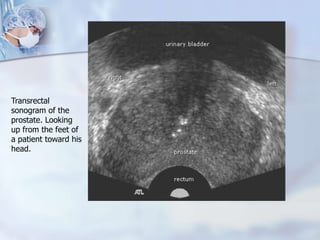

Transrectal

sonogram of the

prostate. Looking

up from the feet of

a patient toward his

head.

kidney.niddk.nih.gov/kudiseases TRUS Guided Biopsy Hypoechoic shows abnormal area needing biopsy